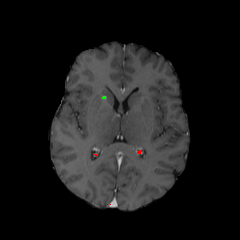

Objectives: This work aims to explore the impact of multicenter data heterogeneity on deep learning brain metastases (BM) autosegmentation performance, and assess the efficacy of an incremental transfer learning technique, namely learning without forgetting (LWF), to improve model generalizability without sharing raw data. Materials and methods: A total of six BM datasets from University Hospital Erlangen (UKER), University Hospital Zurich (USZ), Stanford, UCSF, NYU and BraTS Challenge 2023 on BM segmentation were used for this evaluation. First, the multicenter performance of a convolutional neural network (DeepMedic) for BM autosegmentation was established for exclusive single-center training and for training on pooled data, respectively. Subsequently bilateral collaboration was evaluated, where a UKER pretrained model is shared to another center for further training using transfer learning (TL) either with or without LWF. Results: For single-center training, average F1 scores of BM detection range from 0.625 (NYU) to 0.876 (UKER) on respective single-center test data. Mixed multicenter training notably improves F1 scores at Stanford and NYU, with negligible improvement at other centers. When the UKER pretrained model is applied to USZ, LWF achieves a higher average F1 score (0.839) than naive TL (0.570) and single-center training (0.688) on combined UKER and USZ test data. Naive TL improves sensitivity and contouring accuracy, but compromises precision. Conversely, LWF demonstrates commendable sensitivity, precision and contouring accuracy. When applied to Stanford, similar performance was observed. Conclusion: Data heterogeneity results in varying performance in BM autosegmentation, posing challenges to model generalizability. LWF is a promising approach to peer-to-peer privacy-preserving model training.